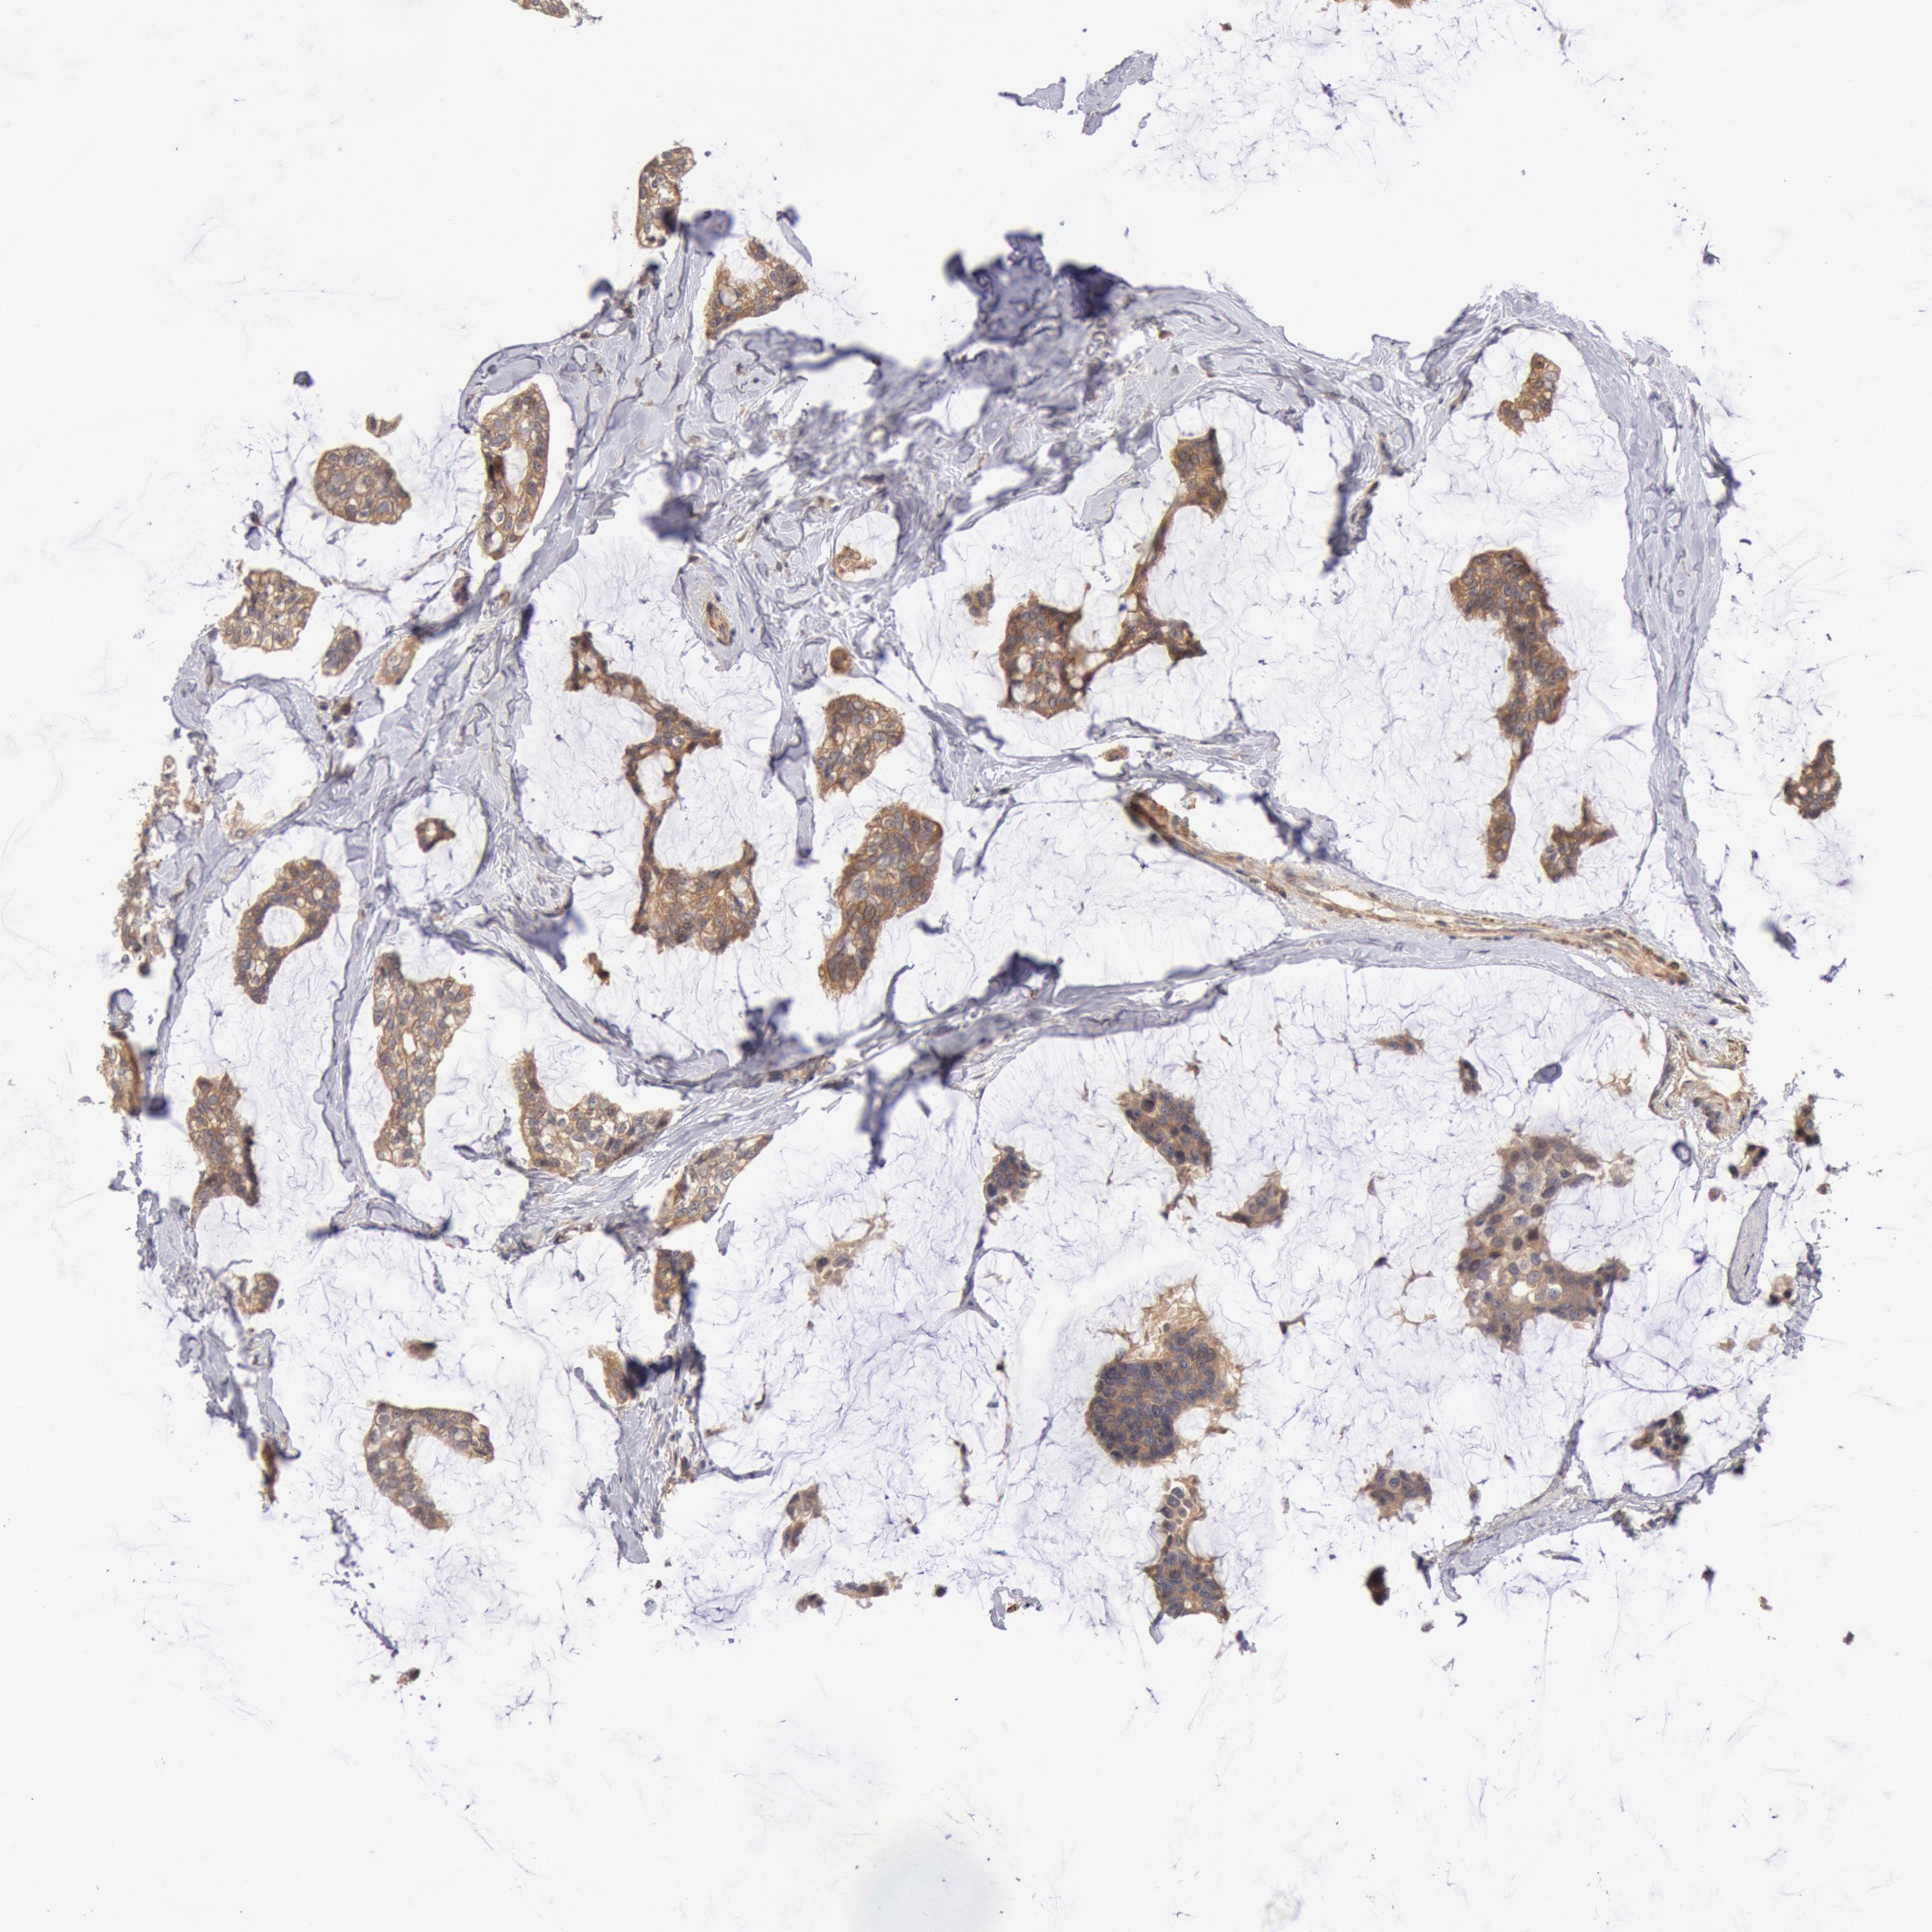

BRCA TCGA BRCA VALIDATION PROTEIN EXPRESSION

ANTIBODIES

AND

VALIDATION